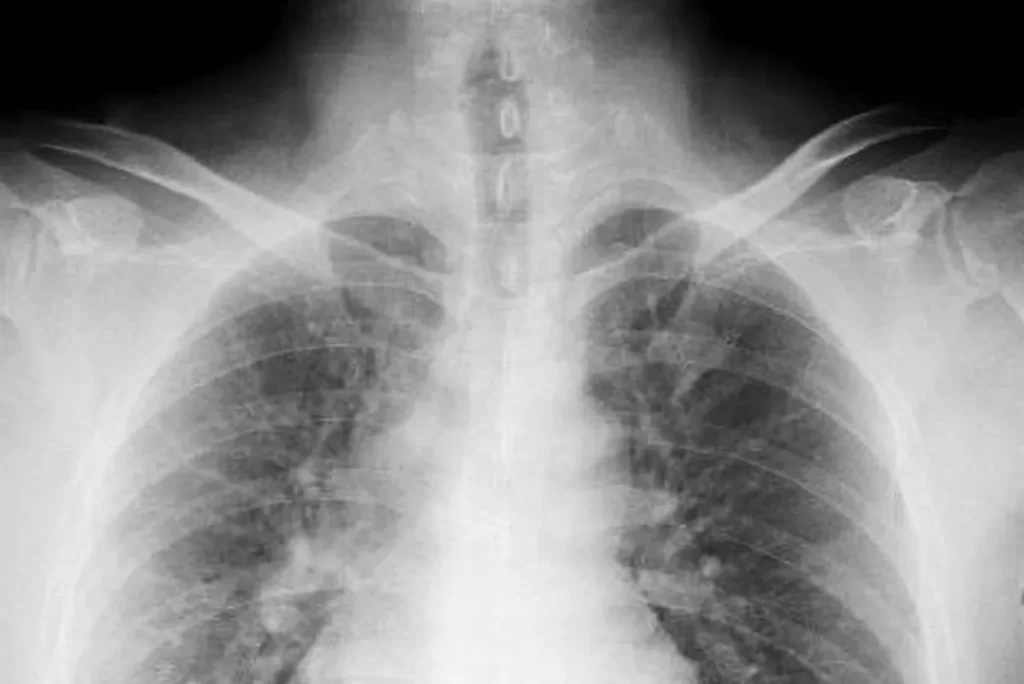

抗がん剤のあと癌が全身に広がって、余命3ヶ月だと言われた膵臓がん女性。

「癌」と書かれたメモ帳を持つ医師が、膵臓がんの原因と中医学の治療法を解説。 こんにちは、李哲です。アメリカの著名な中医学先生:倪海厦(ニハイシャ)先生の治療例、故事篇專講案例給大家聽(漢唐中醫倪海廈撰寫)(2005-5-12発表)を翻訳しました。 抗... -